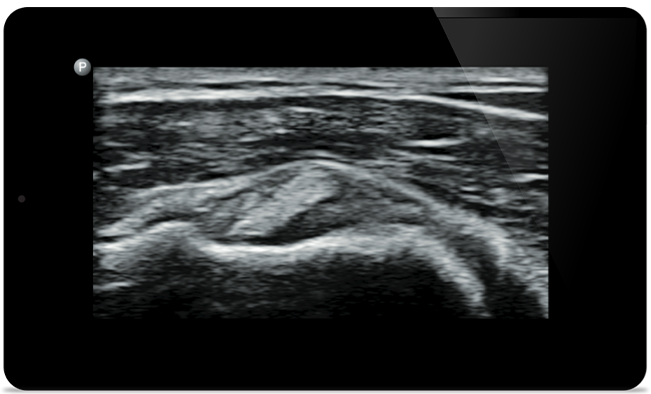

Lumify helps you see the fine details in muscles, joints, ligaments, tendons and cartilage to make a more accurate diagnosis of injuries.

Lumify can help you assess patients from head to toe, whether it’s plantar fasciitis, tendonitis or bursitis in the patellar tendon, or even shoulder instability in the rotator cuff.

SonoCT reinforces real tissue imaging while eliminating random artifacts. This technology produces images superior to conventional imaging in up to 94% of patients.